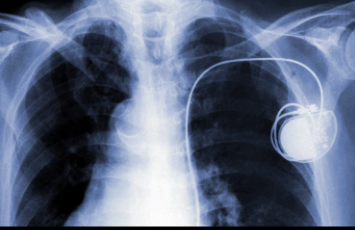

在疫情防控、患者救治等过程中,智能传感器的应用十分广泛。在防疫工作中,对体温筛查起到重要贡献的红外体温计设备,就是典型的红外传感器技术应用。呼吸机中则集成了气体质量、流量、压力、湿度、温度和磁敏等传感器。救护氧舱、ICU病房以及住院隔离区环境监测等,也都离不开气体传感器的支持。